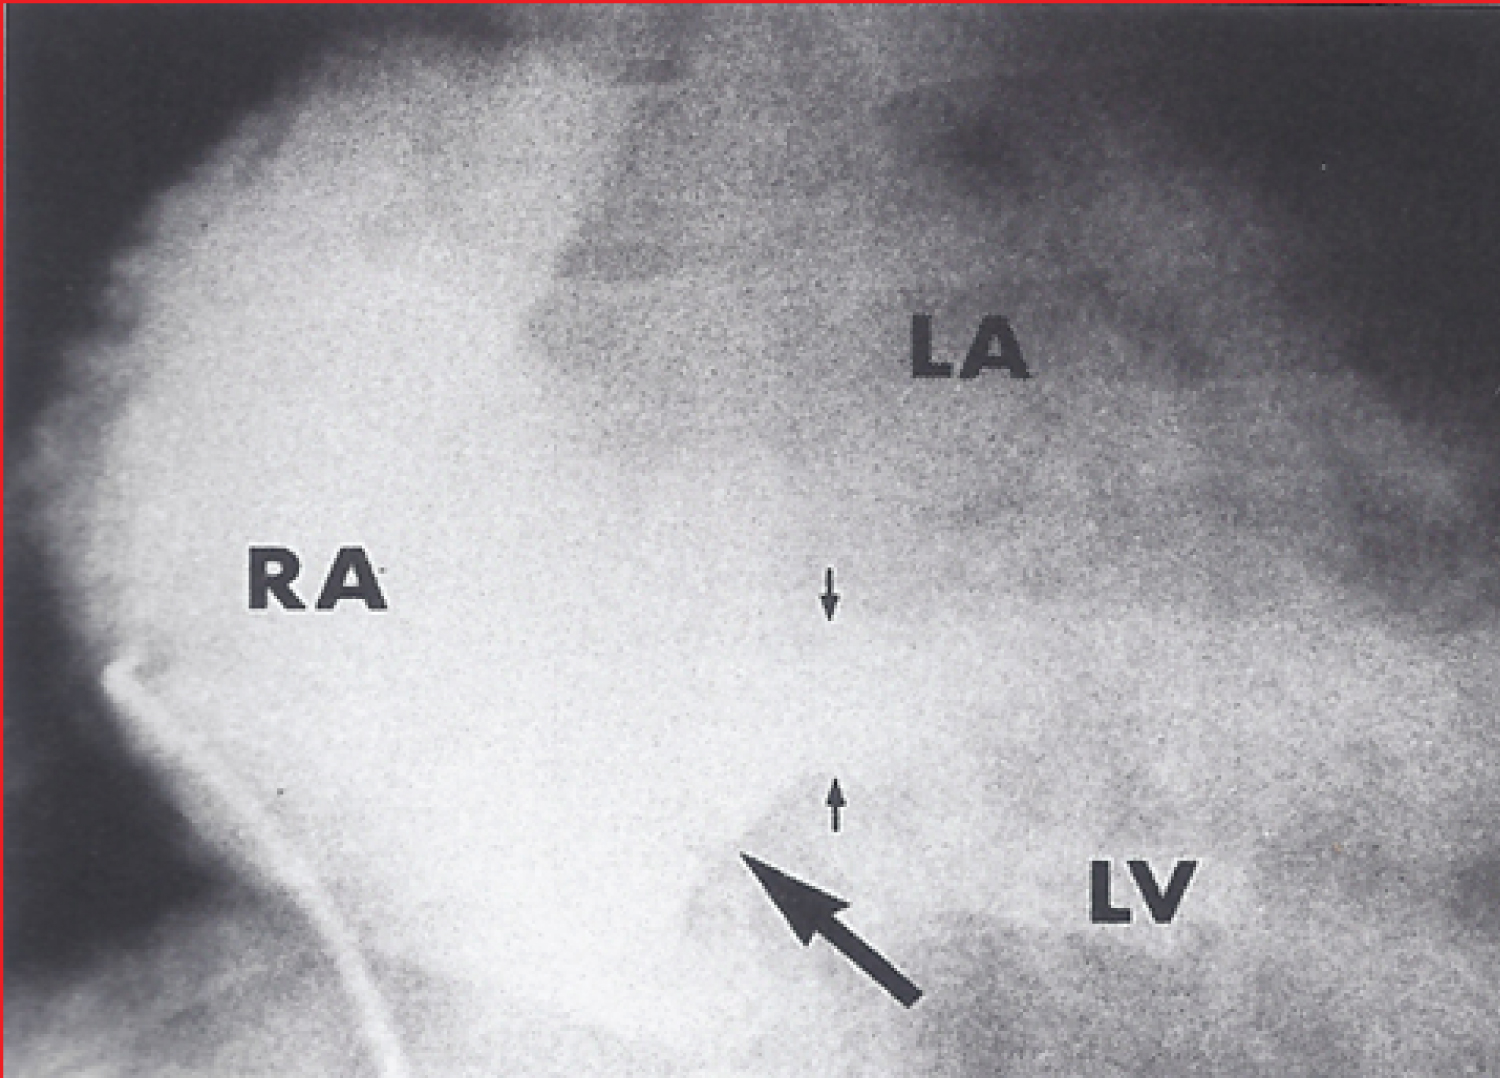

Figure 7: A) Selected right atrial (RA) cineangiographic frame in postero-anterior view prior to opacification of the left atrium (LA) in a patient with tricuspid atresia with Ebstein's malformation. The contrast material delineates the atretic tricuspid valve and is shown by small unlabelled arrows. This is rounded and extends more to the left than in other tricuspid atresia cases; B) Right atrial angiographic frame from a patient with classic tricuspid atresia is shown for comparison with figure A. This frame is frozen prior to full opacification of the LA [41].

RAA: Right Atrial Appendage; SVC: Superior Vena Cava. View Figure 7